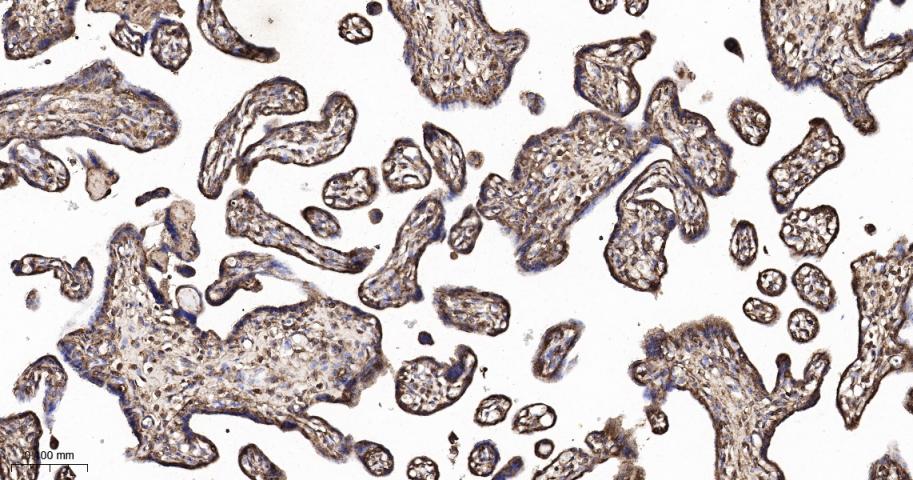

Paraformaldehyde-fixed, paraffin embedded Human Placenta; Antigen retrieval by boiling in sodium citrate buffer (pH6.0) for 15 min; The section was incubated with CDT2 Monoclonal Antibody, Unconjugated (bsm-61709R) at 1:200 overnight at 4°C, followed by conjugation to the bs-0295G-HRP and DAB (C-0010) staining.